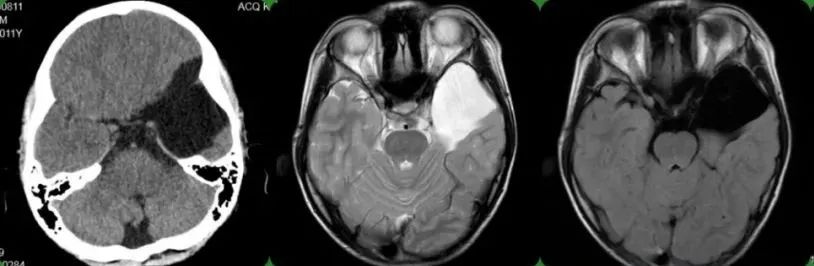

可遗憾的是, 男孩的这些症状并没有像运动发育迟缓那样自行消失, 上述症状一直持续存在,无明显改善,并有加重的趋势 ,今年8月,家长才带着男孩就诊于当地医院, 行头颅MRI检查后:提示“左侧中颅窝巨大蛛网膜囊肿”,大小约6x5cm,累及鞍区,建议转上级医院治疗。

术前检查

为进一步治疗就诊于昆明三博脑科医院,门诊以“左侧中颅窝蛛网膜囊肿”收入神经外科二病区, 院长张永力 详细查看患者、询问病史、查体及阅片后分析指示,结合患者病史、症状、体征及辅助检查, 患者目前诊断明确为:左侧中颅窝蛛网膜囊肿,有明确的手术指征,择期予以“左侧额颞开颅蛛网膜囊肿切除造瘘术”治疗。